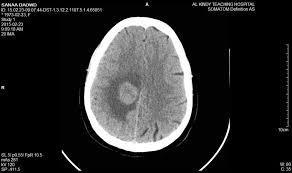

3.2 Computed Tomography (CT): CT exam is a crucial test that allows healthcare specialists to diagnose intracranial diseases,includingtumors,anddetectdeviations.AliteraturereviewconductedbyWangetal(2021)concludedthatthe testhadasensitivityof85%andaspecificityof89%whendiagnosingcerebralpalsy.RecentinnovationofCTwithmultidetector allowed for the improvement of spatial resolution and reduction of the radiating dose which observed in emergencycases.Inadditiontothis,spectralCTtechnologyalsooffersapremierimagemalignantsinfrombenignlesions.